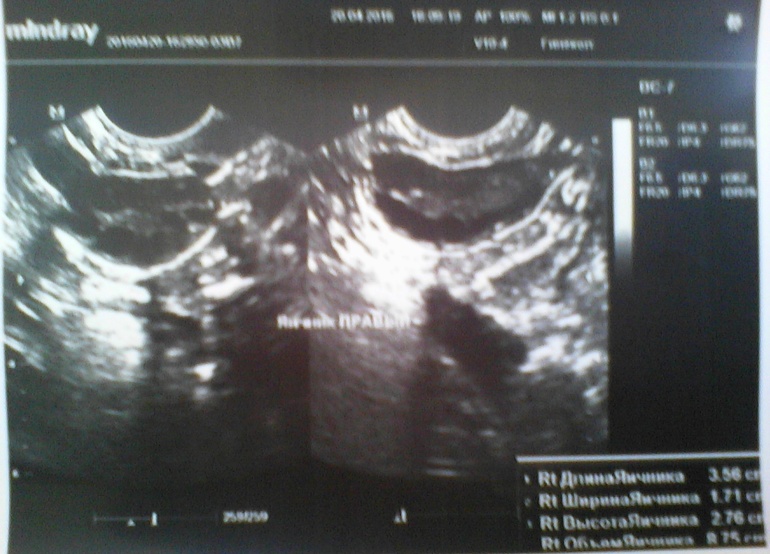

Сегодня 15ДЦ, решила сходить на УЗИ, проверить как-там мои фолики в этом цикле и опять ..........ДФ нет!!!!! Уже третий цикл подряд я без О!!!Получается, что этот цикл пролётный, в следующем только сдам гормоны и только потом, на 3 цикл мне уже хоть что-нибудь назначат(((((К слову БТ высокая в первой фазе, средняя 36,8!Последние два цикла были 20 и 25 дней....посмотрим, что будет на этот раз!

Результаты УЗИ прилагаю!